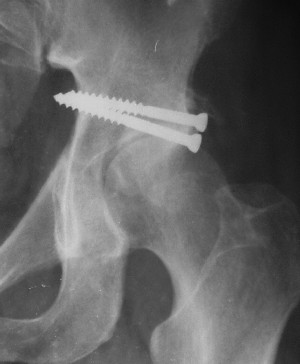

Послеоперационный снимок боковой 5/06/03

Больной 18 мая 2003 года в автоаварии получил перелом левой вертлужной впадины, вывих бедра. Госпитализирован в один из стационаров области.Вывих вправлен. В последствии бедро вывихивалось еще дважды. На консультацию был представлен снимок от 19.05.03г., больной переведен к нам 3.06.03г. Снимок при поступлении - перелом впадины, задне-верхний вывих бедра. 05.06.2003 г. выполнено открытое вправление вывиха левого бедра и остеосинтез стенки вертлужной впадины двумя винтами. Послеоперационный период без осложнений. Объем движений в левом тазобедренном суставе восстановился полностью. Выписан на амбулаторное лечение в удовлетворительном состоянии с рекомендациями 3 месяца ходить на костылях без нагрузки на оперированную конечность. На контрольных рентгенограммах левого тазобедренного сустава 13.10.2003 г. - признаки консолидации перелома; плотность, форма головки и состояние суставных поверхностей удовлетворительные. Разрешена дозированная осевая нагрузка, на конечность с использованием дополнительной опоры. 19.12.2003 г. больной обратился с жалобами на боли в левом тазобедренном суставе. На рентгенограммах левого тазобедренного сустава 19.12.2003 г., 20.02.04г. - асептичекий некроз головки бедра. 5.04.04г. - эндопротез. Сейчас ходит без трости, не хромает. Особенность эндопротезирования - при удалении винтов прослежена линия перелома заднего края впадины и предложено установить чашку несколько меньшего диаметра, чтобы она была покрыта несломанной частью.